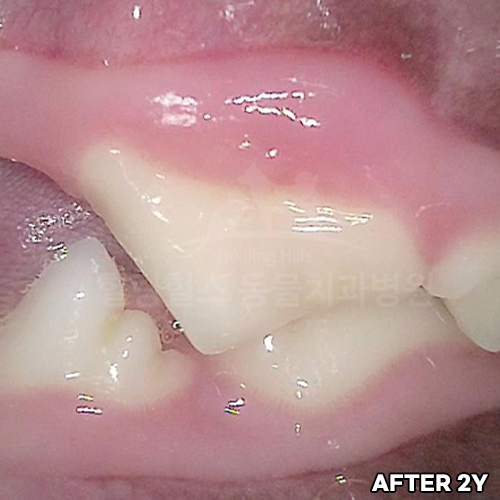

치아뿌리까지 파절된 강아지어금니 빨갛게 부어오른 잇몸치료~ 2년 뒤에 재생된 잇몸뼈 CT로 확인! 모든 동물병원에서 발치하자고 했지만 힐링힐스동물치과병원에서 되살려진 어금니!